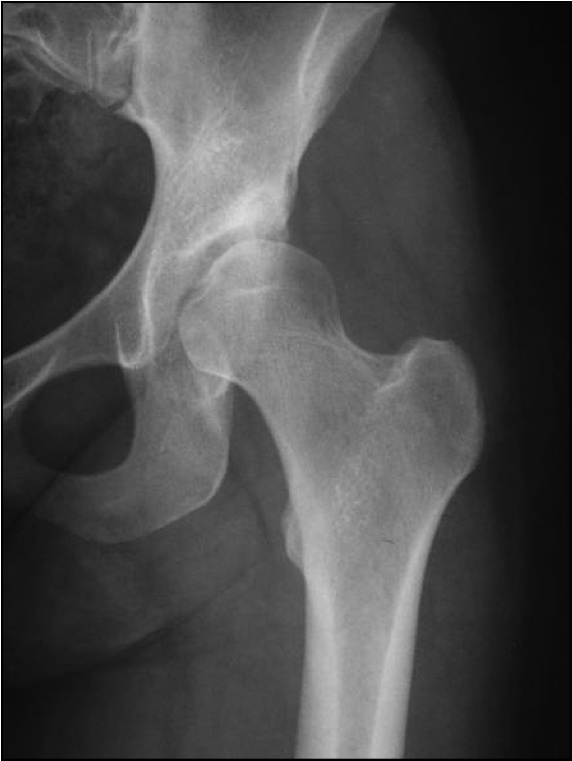

Wir sollen ein Programm schreiben und dann mit GUI ausführen lassen. Das Programm soll ein Röntgenbild (Oberschenkelknochen s. Anhang) einlesen und selbständig erkennen ob es sich um die Aufnahme eines linken oder rechten Oberschenkelknochen handelt.

jetzt die frage wie sollte ich das am besten machen? hat jemand ne idee? Die hochgeladene Datei ist ein linker Knochen. Habe mir evtl. überlegt den Knochen vertikal zu teilen. Danach könnte das Programm gucken auf welcher Bildseite mehr weiße Pixel vorhanden ist und daraus schlussfolgern ob es ein linker oder rechter Knochen ist. Denn wenn z.b. bei einem geteilten bild mehr weiße pixel auf der linken seite sind dann handelt es sich um einen linken knochen und umgekehrt. Muss dazu sagen, dass der Anspruch NICHT der ist, dass das Programm bei jedem Bild funktioniert. Das wäre z.b. eine Idee. Ob es mit Matlab klappt und wie weiß ich nicht deswegen bin ich für jeden Hilfe dankbar!

| Beschreibung: |

| Dateiname: |

Femur.jpg |